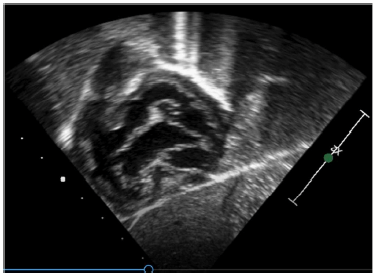

Assinale a opção que contém a afirmação que pode ser seguramente obtida, a partir da imagem ecocardiográfica a seguir.